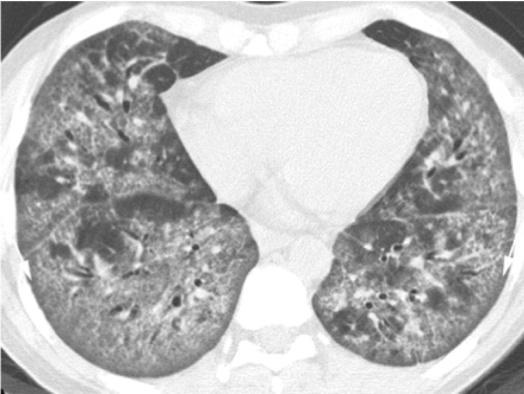

Is this UIP?

This is not UIP because there too much ground glass (too hazy)